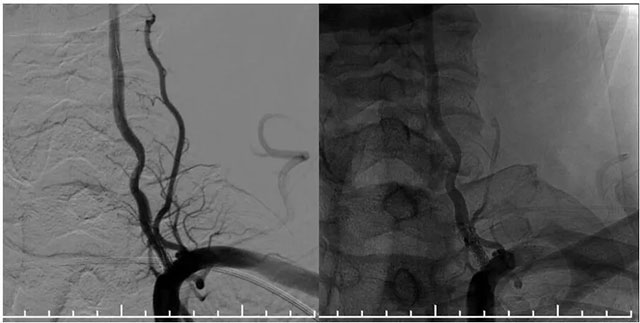

再次超选至左侧锁骨下动脉近椎动脉开口处,单次造影后明确开口狭窄程度,测量狭窄段长度及近远端血管直径,选取合适球囊。随后在微导丝辅助下通过支架内再狭窄段超选至左侧椎动脉V2段,选用2.5*15球囊,沿微导丝到位于狭窄段,球囊扩张至8atm,再次行椎动脉造影,血流有所改善。再次将球囊下移,球囊扩张至14atm,撤除球囊后行即刻造影示血流较前通畅。选择3.5*15药物洗脱球囊,超选至狭窄处,予以6atm,后撤除球囊,行即刻造影示血流较前明显改善,再次行椎动脉造影双侧大脑后动脉及基底动脉血流通畅。

▲ 药物洗脱球囊在微导丝导引下到位于左侧椎动脉支架内,充分扩张药物球囊使其贴壁

▲ 球囊扩张后,支架内狭窄明显改善,支架贴壁良好